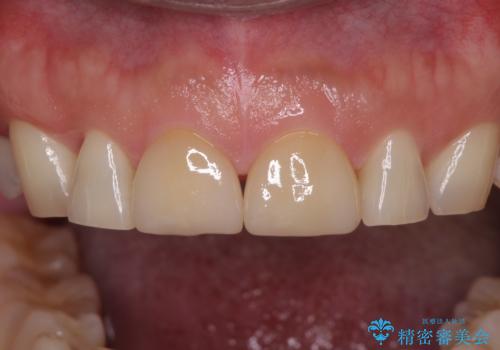

- 前歯の目立つ隙間を気にして来院された患者様です。

高校生の頃に矯正治療を行ったものの、強い咬合力により上顎が拡大され、正中に隙間ができてしまいました。

通常では歯の周囲全体を削った上でクラウンを装着することが多いのですが、咬合力が非常に強く、クラウンではセラミックが欠けてしまう可能性が考えられたため、咬合を変えることとのないラミネートベニアにて治療を行うこととしました。

ラミネートベニアは切削量が少ないことがメリットとしてあげられますが、色調を周辺と合わせられないこと、接着境界線が長く汚れや歯石が溜まりやすいことがデメリットとして考えられます。

また、接着境界線にむし歯がある場合には適用外となるなど、適用症例を選ぶため、治療に際して担当医としっかりと相談することが大切です。